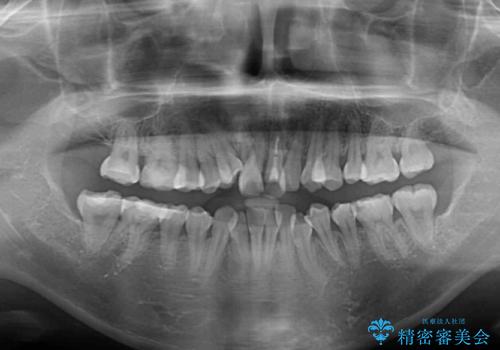

狭い上顎骨を拡大 著しい叢生を抜歯矯正で改善

- 上顎の著しい叢生と奥歯の咬みにくさを気にして来院された患者様です。

骨格的に上顎は狭く、下顎は右側にシフトしていたため、右側臼歯はクロスバイトとなっていました。

上顎骨を急速拡大装置により拡大し、ワイヤー装置による抜歯矯正治療を行うこととしました。